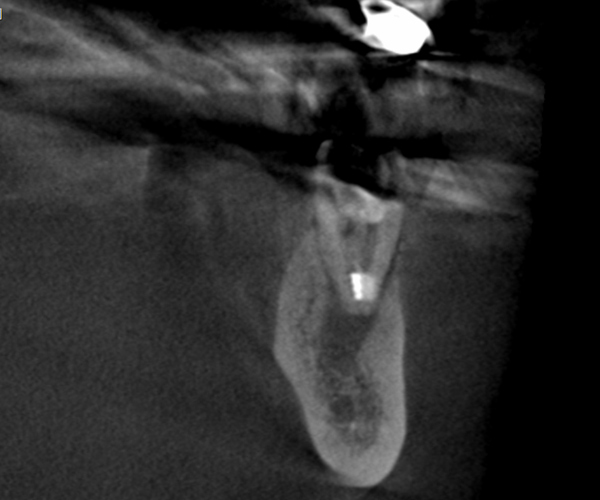

症例2歯性上顎洞炎(副鼻腔炎)

Before

歯性上顎洞炎(副鼻腔炎)

根尖病巣により洞底膜がラッパ状に開いている。

After

6ヶ月後のCT

洞底膜はきれいに再生され病巣は消失しております。